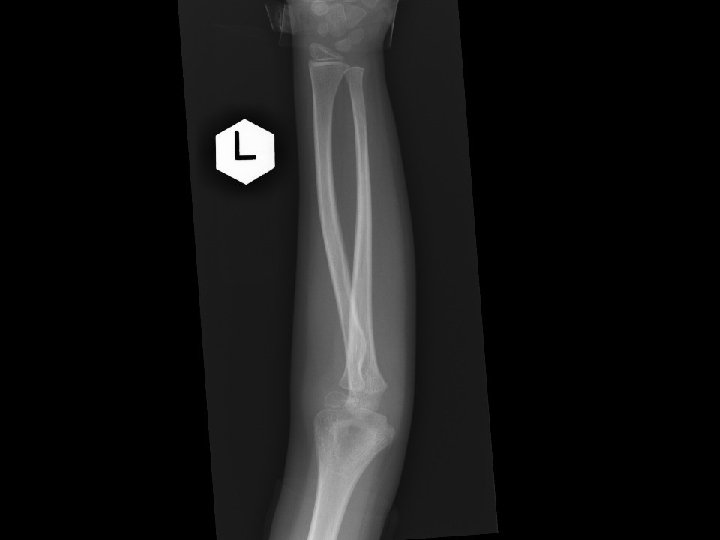

Case 2 • F/6 • Left elbow contusion after S/F in 2 months ago • c/o: persistent pain after the injury • PE: tenderness and swelling over her left elbow. ROM: 0 -90 degree. No distal neurological deficit elicited. • X rays left elbow was taken

Questions • 1) what is the diagnosis? • 2) what is the associated injury to look for? • 3) what is the management?

Answers • Dislocated radial head • Plastic deformity of ulna shaft • Dx : greenstick Monteggia # with anterior radial head dislocation • Rx : ulnar correctional osteotomy + CR radial head +annular ligament repair